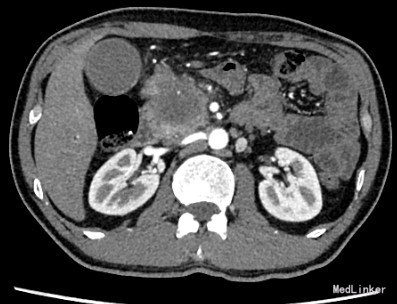

查体:身目重度黄染,上腹部轻压痛; 辅助检查: 白细胞WBC:10.96; 血红蛋白Hb:145g/L;血小板PLT:241x10^9/L 丙氨酸氨基转移酶ALT 357 U/L ;天冬氨酸氨基转移酶AST 191 U/L;白蛋白ALB 40.9 g/L ;总胆红素TBIL 151.2 umol/L;直接胆红素DBIL 85.8 umol/L 肿瘤标记物: 甲胎蛋白(AFP) 5.00 ug/L 0.00 - 20.00 ;癌胚抗原(CEA) 9.19 ug/L ↑ 0.00 - 5.00 ;CA125 71.00 U/mL ↑ 0.00 - 35.00 鳞癌抗原(SCC) 0.90 ug/L 0.00 - 1.50 ;CA19-9 〉12000.00 U/mL CT:平扫胰体尾部萎缩,胰头区不规则肿大,局部可见类圆形软组织肿块影,大小约44×43mm,边界模糊,内部密度不均,其内可见斑点状钙化灶,并见更低密度区。增强扫描正常胰腺组织明显强化而肿物轻度强化,显示较清楚;强化不均匀,中央有低密度坏死区。肿块与十二直肠降段分界不清,病变包绕肠系膜上静脉,血管见充盈缺损影,胰头周围及腹膜后见肿大的淋巴结影。、、、 1.胰头癌,侵犯十二指肠降段及肠系膜上静脉,胰周及腹膜后多发淋巴结轻度肿大。 2.肝S7病灶,高度怀疑转移瘤。 超声造影提:胰头病变:考虑胰头Ca。 肝S7病变:考虑MLC。 肝内外胆管弥漫性扩张。胆囊壁增厚。腹膜后淋巴结肿大。脾脏超声检查未见异常。